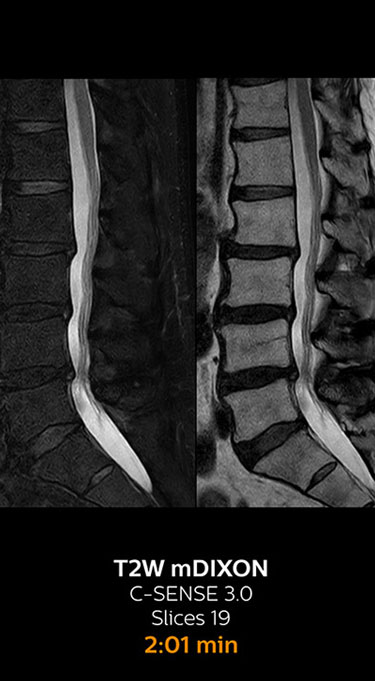

Fast MRI of lumbar spine

which corresponds to 34% reduction.

With Compressed SENSE, the scan time for the routine lumbar spine examination at KNC was reduced from 11:41 to 8:17 minutes,

MRI examination of the lumbar spine with Compressed SENSE

Ingenia 3.0T CX

Scan time 8:17 min. (was 11:41 min. without Compressed SENSE)